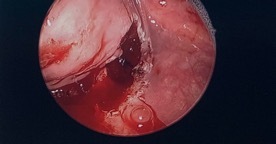

Two days following imaging, the patient was taken to the operating room for esophagoscopy with dilation and micro suspension direct laryngoscopy. The patient was instructed to withhold food and fluids 8 hours prior to her procedure. The laryngoscope revealed no anatomical abnormalities within the larynx or trachea. Within the hypopharynx (most inferior portion of the pharynx), a large midline web (red arrow in Figure 2) extended from the posterior cricoid area (region of the throat just behind the cricoid cartilage) and right pyriform sinus (subsite of the hypopharynx that act as a lateral channel for the passage of boluses into the esophagus) to the posterior pharyngeal wall, essentially separating the right pyriform sinus from the remainder of the pharyngeal inlet.